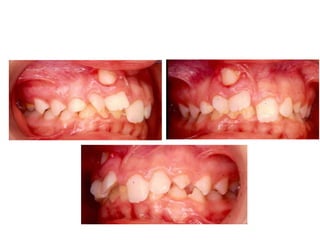

TRANSPOSIÇÃO TOTAL - CANINO COM INCISIVO LATERAL MANOBRAS PARA CORREÇÃO DA ROTA DE ERUPÇÃO